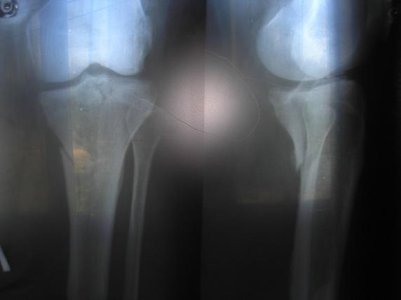

Б/берцовой кости левой голини .

15 июля наложили гипс нога не болела не зависимо как бы не вертела ею 15 августа самостоятельно сняли гипс и начала самостоятельно разрабатывать ногу , делать ванны с морской солю в теплой воде, втирать пихтоватое масло в перелом . 16 августа начала болеть нога 17.08.09 сделали снимок, а перелом как такой как был месяц тому назад совсем не зажил.